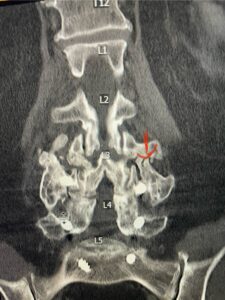

In patients who have lumbar spinal stenosis and significant cardio/pulmonary conditions, surgery is the last resort. However, some patients with these conditions may fail all means of conservative management where surgery becomes their only option for relief. In those patients, one should strive to do the least complex surgery that is necessary to get the job done for them. In this case study, we are confronted with a new problem in a 78 year-old male patient that was in poor medical condition who had had two prior lumbar laminectomies with resultant fusion and instrumentation from L4-S1. There was now retrolisthesis of L2-3 with severe stenosis (Fig.1)

Fig 1a: Sagittal T2 weighted lumbar MRI demonstrating severe L2-3 stenosis (red arrow)